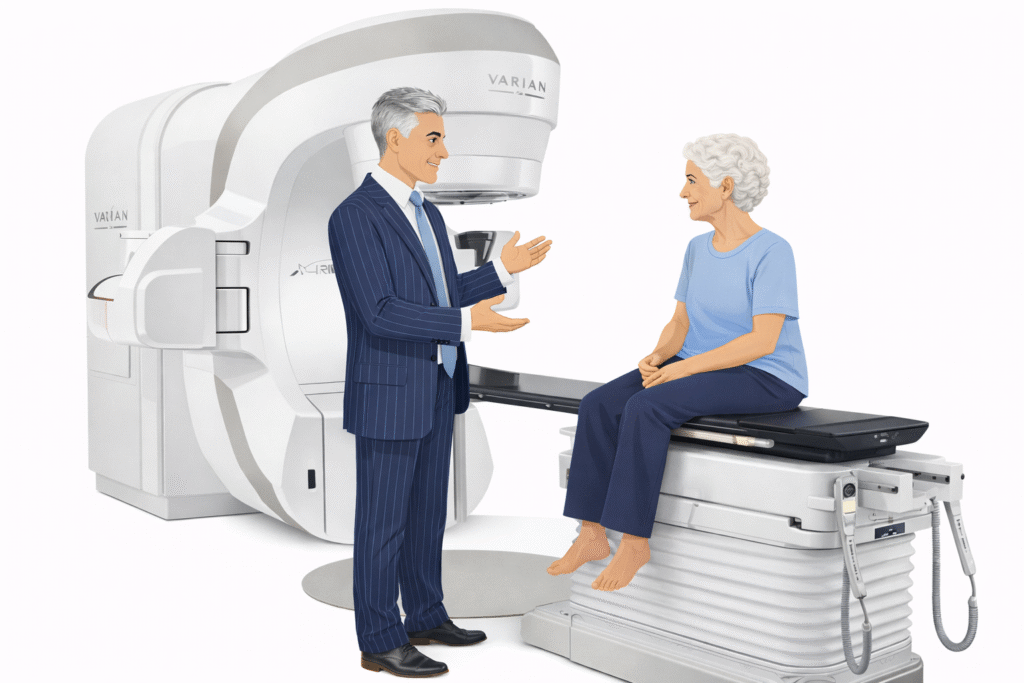

How Pinpoint Radiotherapy Can Help

At Pinpoint Radiotherapy, we specialise in delivering precise, advanced treatments like Stereotactic Radiosurgery for brain metastases. Our expert team uses the latest technology to tailor each patient’s treatment plan, ensuring that radiation is delivered with the utmost precision. We understand that every patient’s journey is unique, and we are committed to providing compassionate care that focuses on both the quality of life and effective disease management.

If you or a loved one is facing brain metastases and considering treatment options, contact Pinpoint Radiotherapy to learn more about how SRS can be part of your care plan. We’re here to support you with advanced, patient-centred care every step of the way.